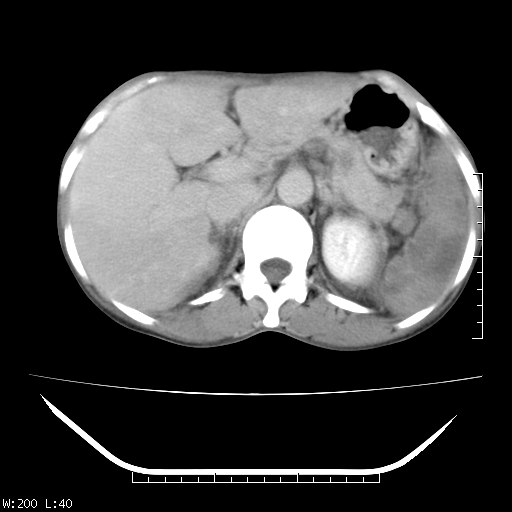

以下是引用zhangqichun5在2007-5-23 23:47:00的发言:[br]肝右叶低密度,脾低米度,左肾混杂密度,考虑是肝癌肾脾转移

以下是引用苯小孩在2007-5-24 13:30:00的发言:[br]肝、脾肿大不均匀强化,脾脏低密度区内见结节样强化.淋巴瘤?考虑为淋巴系统或血液系统疾病,建议骨穿. [br] [br]

以下是引用jsgdoctor在2007-5-24 7:53:00的发言:[br]考虑为淋巴系统或血液系统疾病,建议骨穿.